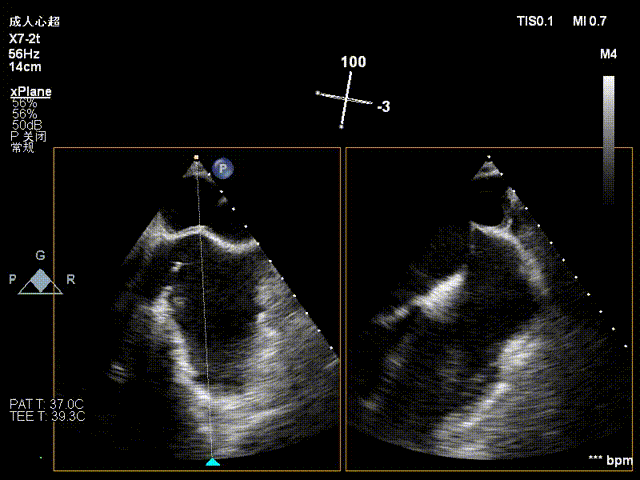

NeoNova®C6(宽6mm)夹合器沿输送系统进入左房,调整夹合器orientation,夹合器抵达3区反流处。

进夹合器

进夹合器调弹道